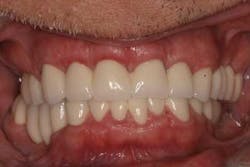

Case study A 58-year-old male with a noncontributory medical history presented to a private practice for a complete rehabilitation of his dentition due to years of bruxism and parafunction. (Fig. 1) After surgical and restorative consultations, a treatment plan was fabricated. The treatment plan included restoring his lost vertical dimension, restoring his natural dentition with porcelain-fused-to-metal full-coverage crowns, and replacing his lost posterior teeth with dental implants. After his vertical dimension was restored with an acrylic bite plate to a position harmonious with TMJ function, crown-lengthening surgery was performed. (Fig. 2)Fig. 2 Six weeks after, the teeth were temporized to develop soft tissue margins/interdental papillae. (Figs. 3 and 3a) The patient was kept in temporaries for three months, during which time an implant was placed in site No. 19. Both the natural dentition and the implant were completed at the same time, three months after implant placement. (Fig. 4) Because of the patient’s occlusal issues, the implant was screw-retained, and the patient was given a maxillary night guard. Three weeks after insertion, the patient presented with a loose abutment screw. The dentist tightened the screw and sent the patient home. This cycle was repeated two more times until the patient presented again with a loose crown, but this time, a fracture implant screw. The dentist attempted to remove the screw with a Cavitron and drilling the implant screw out to release preload, but to no avail. The case was then referred to my office for implant removal.